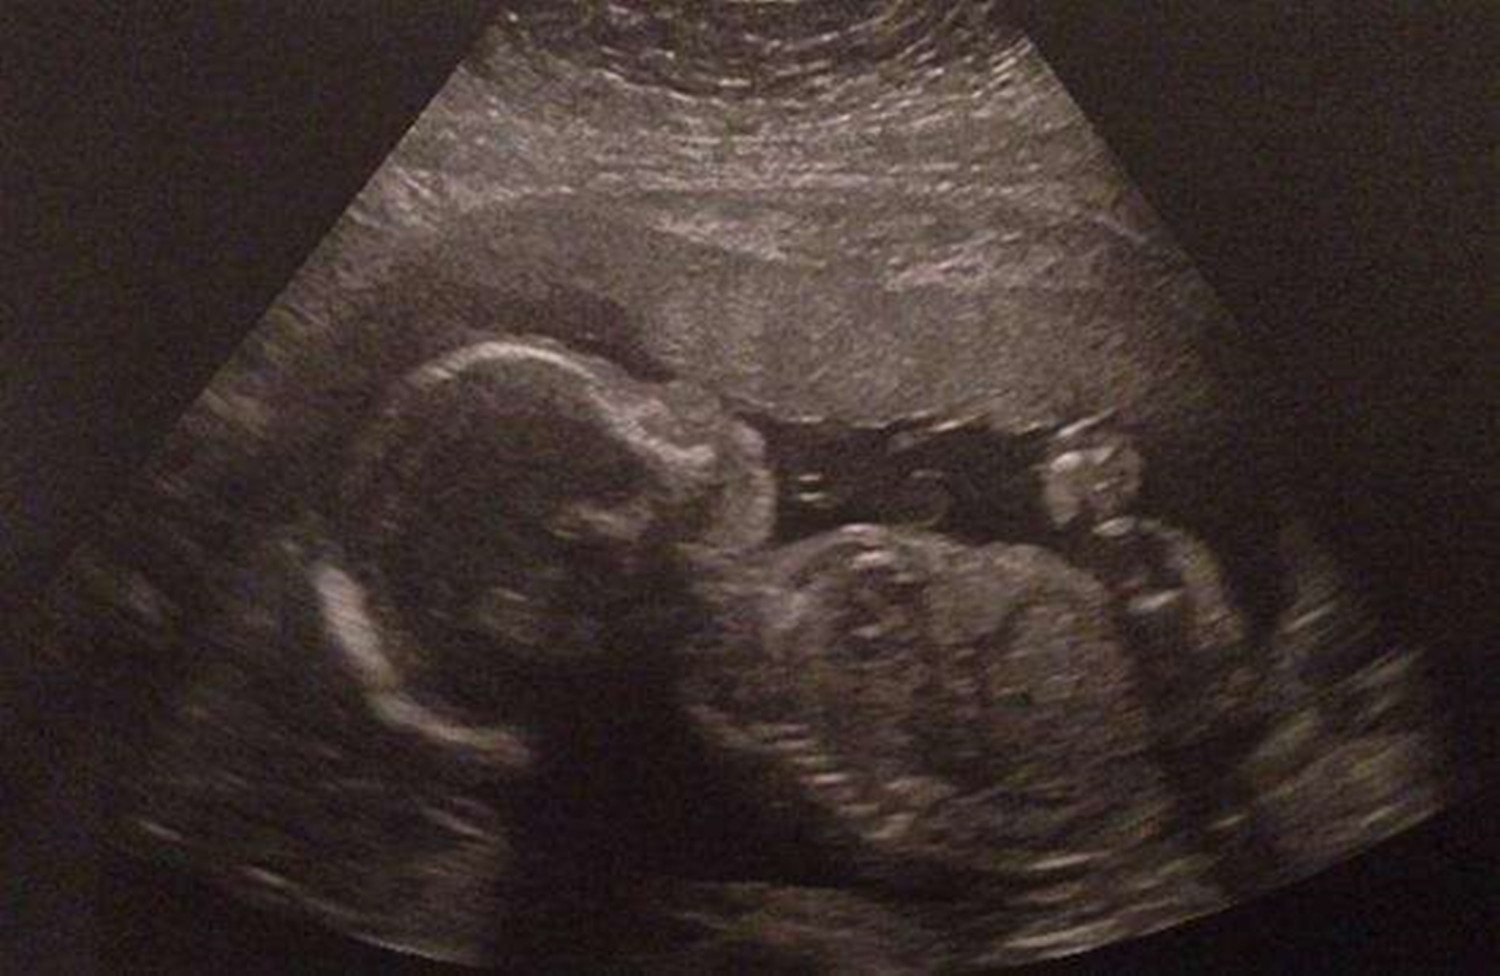

胎动,是指胎儿在子宫腔里的活动冲击到子宫壁的动作。胎儿在子宫内伸手、踢腿、冲击子宫壁,这就是胎动。

胎动是现代医疗技术中,辅助视察胎儿在子宫内是否健康的一个较为有效的办法。

一般孕妈满四个月后,开始感到胎儿的明显活动,医生或孕妇可以根据胎动的次数多少、快慢强弱等来检测胎儿的安危。